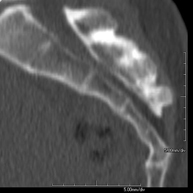

- TC Esternón Exploración radiológica que mediante un sistema de rayos X y detectores que giran alrededor del paciente, reconstruyendo las imágenes por ordenador, permite el estudio detallado del esternón. Exploración radiológica que mediante un sistema de rayos X y detectores que giran alrededor del paciente, reconstruyendo las imágenes por ordenador, permite el estudio detallado del esternón.

- TC Parrilla costal Exploración radiológica que mediante un sistema de rayos X y detectores que giran alrededor del paciente, reconstruyendo las imágenes por ordenador, permite el estudio detallado de la parrilla costal. Exploración radiológica que mediante un sistema de rayos X y detectores que giran alrededor del paciente, reconstruyendo las imágenes por ordenador, permite el estudio detallado de la parrilla costal.